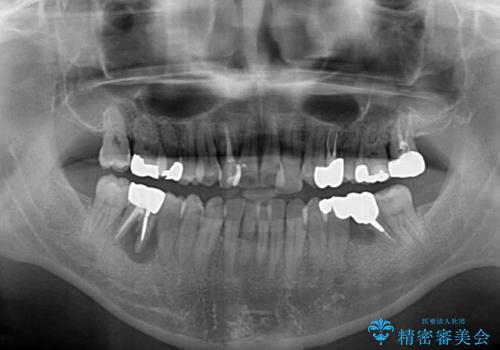

左右下顎の大臼歯は、ともに歯根が破折しており、抜歯が必要な状態でした。

放置したことで炎症による骨吸収が顕著であるため、骨造成を併用してインプラント埋入を行うこととしました。

咬み合わせは受け口傾向であり、上顎前歯の叢生が顕著であったことから、第1小臼歯抜歯による矯正治療も検討しましたが、下顎大臼歯を左右ともに抜歯するため、非抜歯による矯正治療を行うこととしました。

矯正治療でインプラント埋入を行い、矯正治療後に気になる前歯と合わせてオールセラミッククラウンによる補綴治療を行うこととしました。